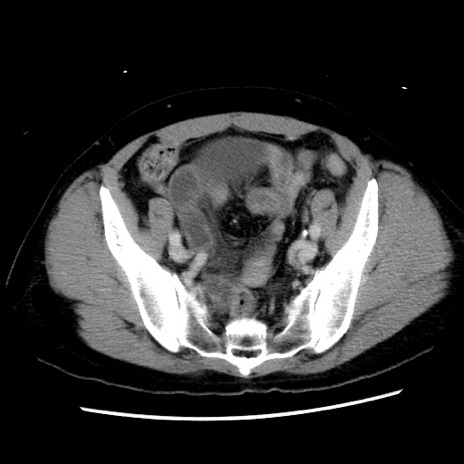

症例10(横断像)

【症例】 50歳代女性

【主訴】 腹痛

【現病歴】前日生レバーを食べた。今朝に排便あり。 昼前に突然発症の腹痛を生じ、当院救急外来を受診した。

【既往歴】 子宮筋腫にてで子宮全摘後

【身体所見】 意識清明、腹部:平坦、軟、下腹部やや左を中心に圧痛・反跳痛あり、筋性防御あり

【データ】WBC 7800、CRP 0.07